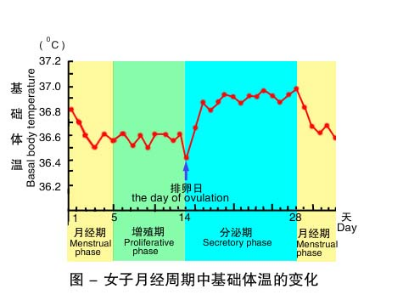

测量基础体温判断排卵期

女性基础体温有周期性变化,月经后半周期若基础体温升高能提示已排卵。正常情况下排卵后体温上升0.3-0.5℃,称双相型体温。如无排卵,体温不上升,整个周期间呈现低平体温,称单项型体温。

温馨提示:如果你的月经不规律或生活不规律,如:夜班、出差、失眠、情绪变化、疾病等,不能用此判断有无排卵。